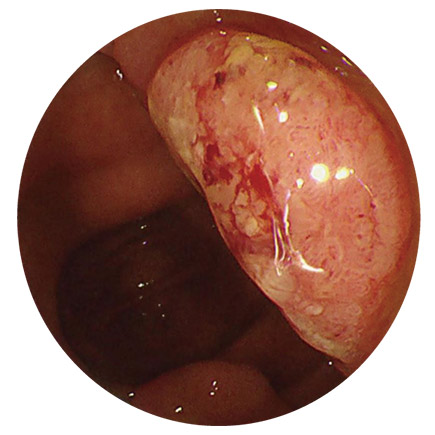

がん

大腸がんのでき始めは、一般的にはポリープ(おでき、いぼのようなもの)の形をしており、当院では、大腸カメラを行ったその場で検査と同時に切除することができます。

内視鏡でポリープを切除する目的は、先々大腸がんに育つ前に「がんの芽を摘む」ことです。

(もし大腸がんになっていたとしても、早期であればその場で切除することが可能なものもあります)